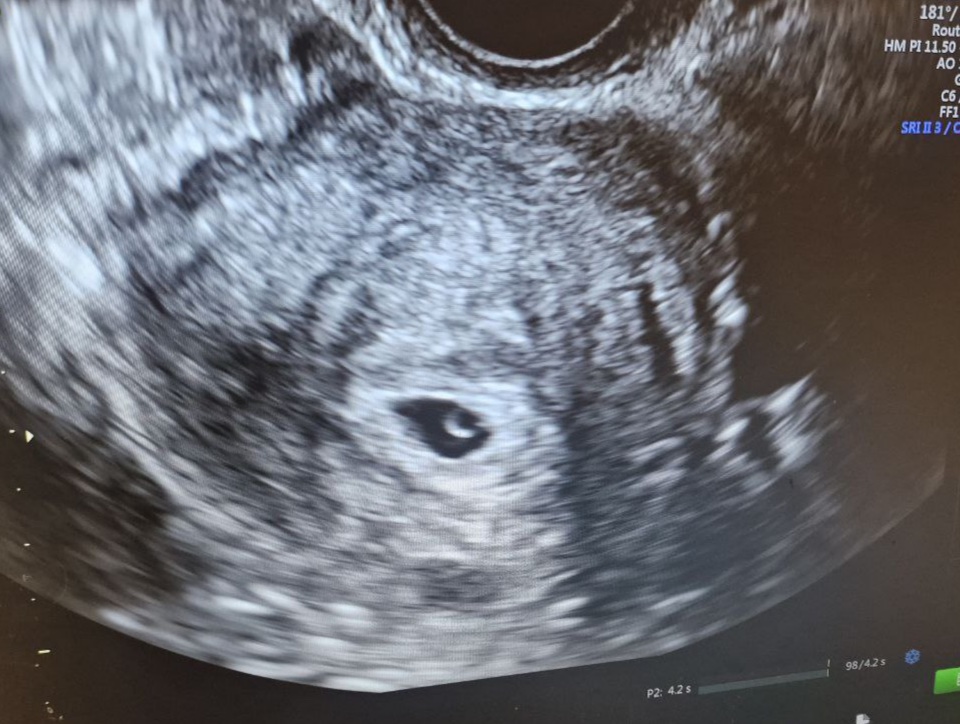

Євген — лікар реабілітаційної та фізичної медицини, Наталя — економіст. Подружжя з Миколаєва протягом трьох років намагалося стати батьками…

Денис та Ірина живуть у місті Кам’янське, Дніпропетровської області. Вони познайомилися, швидко вирішили жити разом і майже одразу заговорили про дитину. Але замість очікуваної вагітності їхня історія почалася з втрати.…

Наталя (29 років) та Антон (32 роки) з Одеси протягом п’яти років жили з діагнозом безпліддя. Причиною став двобічний гідросальпінкс патологія маткових труб, яка унеможливлює природне зачаття та часто потребує хірургічного лікування.…

Це реальна історія пацієнтки медичного центру «Мати та дитина», яка у 2024 році звернулася з діагнозом «безпліддя протягом двох років». Причиною стали непрохідні маткові труби один із частих факторів, що унеможливлює природне зачаття та потребує допоміжних репродуктивних технологій.…

Пацієнтка Олена звернулася до лікаря репродуктолога Віталія Радька у віці 39 років. Вона вже мала досвід материнства, але протягом двох років не могла завагітніти вдруге. Діагноз: вторинне безпліддя. Бажання стати мамою знову залишалося таким же сильним, а емоційне навантаження від повторних невдач лише посилювалося.…

Я добре памʼятаю той серпневий день 2024 року. У мій кабінет зайшла висока красива жінка у військовій формі. Шість років безпліддя. Чоловік теж військовий. За її плечима — служба, бойові ротації, лапароскопія і невдала спроба завагітніти…

Вона прийшла до мене з одним великим бажанням: стати мамою. Пацієнтка, 1985 року народження, з виснаженим оваріальним резервом: АМГ 0.37, лише один фолікул у кількох послідовних циклах…

Історія Оксани та Миколи, пари, яка виграла проєкт #ЛелекаПрилетить. Після тривалих спроб і лікування безпліддя вони стали батьками двійнят завдяки лікарям…

Кілька років тому лікарі повідомили Тетяні з Черкас, що без ЕКЗ вона не зможе стати мамою. Під час лапароскопії було видалено одну трубу, а інша виявилася непрохідною. Але Тетяна не опустила руки. Вона продовжувала шукати фахівців, які допомогли б здійснити її мрію — народити дитину.…